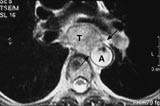

For å utføre preoperative bedømmelser, både for tynntarm og colon, benyttes også multiplanare bildeserier. Det er lite publisert litteratur om MR og tarm, og det er antakeligvis også begrenset hvor mye denne undersøkelsen brukes. Ved Ullevål sykehus gjør vi rutinemessig en preoperativ undersøkelse av anorektal cancer (fig 5). Resultatene synes å bli bra, men lenger oralt i tarmene, er det subjektive inntrykket at vi får lite ut av det. Dette er i overensstemmelse med litteraturen, preoperativ stadieinndeling av cancer recti med MR er innarbeidet som rutine. Det er også vanlig å benytte MR ved kontroller etter operert cancer recti (14).

Figur 5   Tumor i rectum (små piler). Tumor sees som en grå masse som buker inn i rectums lumen, den kommer ikke gjennom eksterne sfinkter (store piler). Det er mulig å skille ut eksterne og interne sfinkter, man aner to lag i kant av tumor, noe som også er nyttig i andre sammenhenger